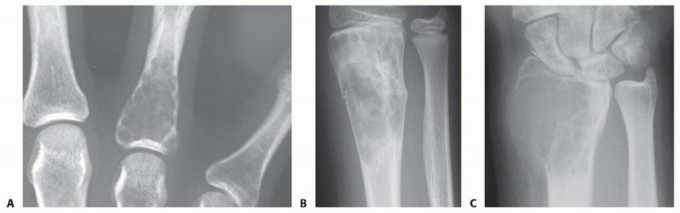

Question 66

A 60-year-old man has pain at the tip of the index finger. A radiograph and biopsy specimen are shown in Figures 40a and 40b. Management should consist of

Explanation